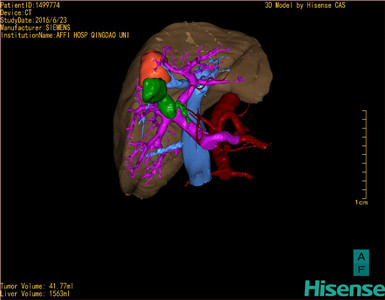

将0.625mm双源薄层CT资料的静脉期和动脉期Dicom格式文件导入海信CAS系统。

通过调节窗宽窗位调整CT序号,对肿瘤,肝实质,胆囊,下腔静脉,肿瘤,肝动脉、门静脉及肝静脉等进行三维重建;系统自动计算肿瘤体积和肝脏体积。

模拟手术操作,自动计算切除肿瘤体积。肝脏体积为1536ml,肿瘤体积为41.77ml,肿瘤体积为肝脏体积2.7%,通过比60-70岁正常肝脏体积为1262.7±284.31ml,通过术前模拟手术,精准判断切除后剩余肝脏体积能耐受,避免肝衰竭发生。

术前手术方案的规划。

术前三维重建:

重建图片